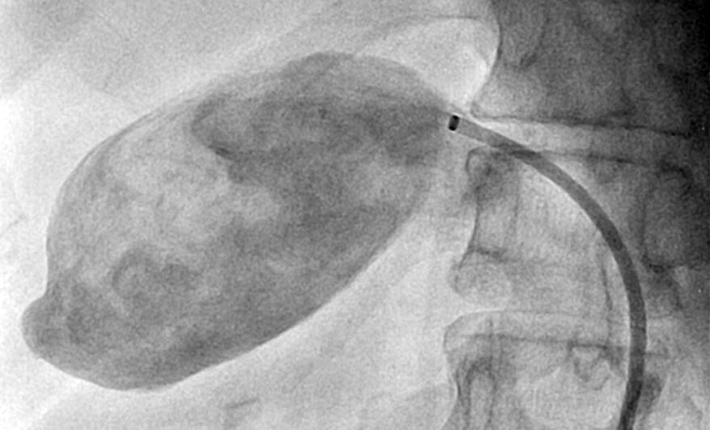

- Angiografia: Um exame invasivo que permite visualizar a artéria hepática e o aneurisma com o uso de contraste radiopaco. Permite evidenciar o tamanho, a forma e a localização do aneurisma, permitindo uma programação terapêutica, além de delimitar a eventual presença de circulação colateral.

A abordagem endovascular vem ganhando espaço no tratamento dos AAH, especialmente em procedimentos eletivos, devido à alta taxa morbimortalidade na cirurgia aberta. A principal vantagem é a menor invasividade, especialmente útil para pacientes de alto risco. Sendo assim, essa abordagem é inicialmente recomendada para todos os AAH que sejam anatomicamente viáveis, ou seja, quando é possível manter a circulação arterial para o fígado. As abordagens intervencionistas no AAH podem ser realizadas através de implante percutâneo de endopróteses para exclusão endovascular do aneurisma, através da oclusão da artéria hepática (por embolização) ou através do reparo cirúrgico aberto da dilatação arterial (ressecção cirúrgica com interposição de enxerto). Em relação às técnicas endovasculares, uma vez que a manutenção da perfusão do órgão distal é importante, o stent recoberto é sempre preferível à embolização em espiral. Os procedimentos reconstrutivos são indicados, principalmente, quando uma vascularização colateral para o segmento hepático relacionado não estiver presente.